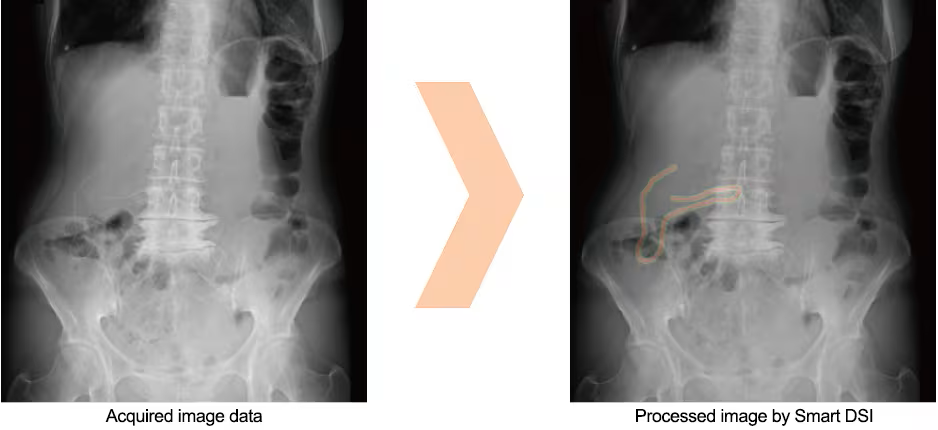

Smart DSI: KI-unterstützte Darstellung von zurückgebliebenen Objekten OPTION

"Smart DSI nutzt KI-Technologie zur Unterstützung bei der Identifizierung von im Körper verbliebenen Objekten. Es hebt Bildbereiche hervor, in denen potenziell chirurgische Nadeln, Gaze mit röntgendichten Fäden und andere Fremdkörper ersichtbar sein könnten.*1)

Von Smart DSI erstelltes Bild *2)

Bildschirmdarstellung mit Smart DSI

- *1) Die in Smart DSI verwendete KI-Technologie (künstliche Intelligenz) ist keine selbstgesteuerte interaktive Lern-KI.

- *2) Verlassen Sie sich bei der Feststellung, ob Fremdkörper im Patienten verblieben sind, nicht ausschließlich auf die Bildverarbeitungsfunktionen von Smart DSI. Treffen Sie Ihre endgültige Entscheidung anhand einer visuellen Überprüfung der Röntgenbilder, der Anzahl der Gazetücher und anderer Methoden.